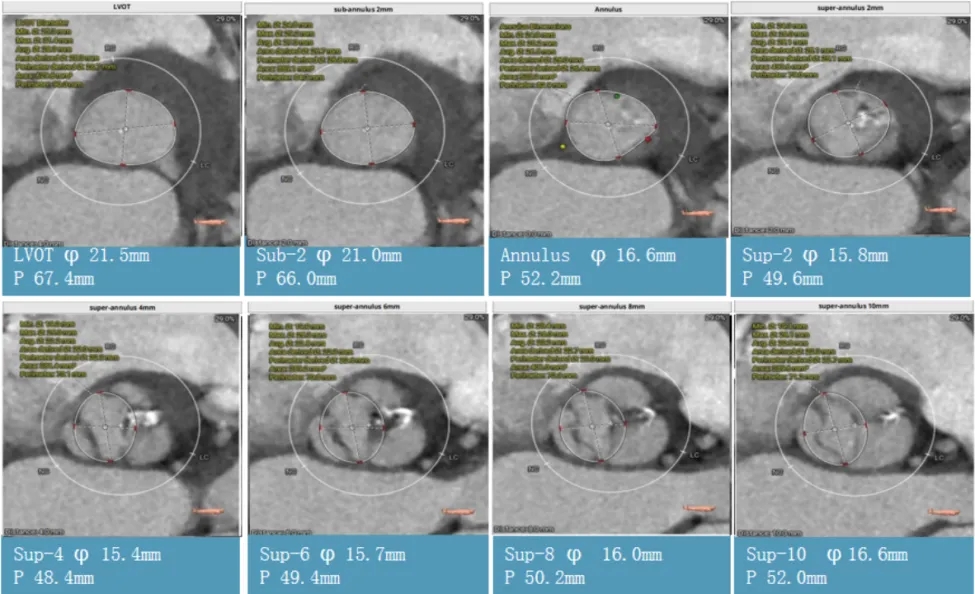

术前CT评估:功能性二叶瓣,左右融合嵴伴钙化,瓣叶增厚,瓣环径26.5,LVOT:28.7,瓣上可打开至23左右,窦部空间可,双侧冠脉开口高度可,主动脉弓大弯侧无明显钙化,双侧髂股动脉内径偏细,右侧股动脉分叉位于股骨头平面中部,左侧股动脉分叉位于股骨头平面中下1/3,建议右侧股动脉入路。

CT影像: